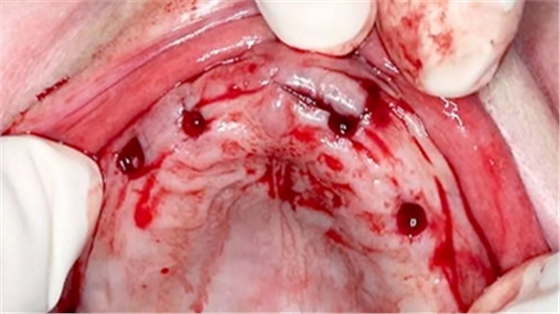

拔除殘根(圖 4),將導板完全覆蓋在黏膜上(圖 5),環(huán)切黏膜瓣(圖 6)

(圖4)